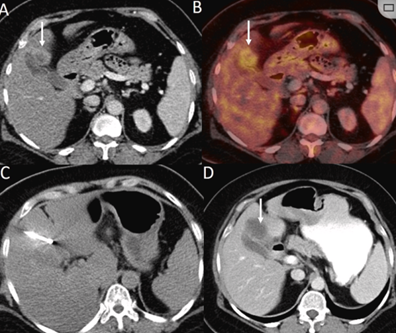

79 歲男性,肝轉移(結直腸癌)腫瘤的完全消融病例

( a ) 軸向 MRI 和 ( b ) 軸向 CT 顯示肝S8段有一個16mm的病灶,鄰近肝緣。( c )冷凍消融期間CT顯示放置了2個冷凍探針,低密度冰球包圍病灶。(d)術后1個月隨訪 CT顯示冰球對應的壞死區域,未見復發。(f)與基線影像(g)相比,12個月后的FDG-PET/CT顯示未見FDG攝取。

(a)軸向CT顯示病變位置毗鄰心臟和上腔靜脈(黑色箭頭)。1個月后的軸向(e)和冠狀位(f)增強CT掃描顯示低密度區域,由于肉芽組織反應引起的邊緣增強。

技術成功100%,92% 的病灶中觀察到腫瘤完全消融。16 名患者 (33%) 出現局部復發。10 名患者 (20%) 因局部復發或腫瘤消融不完全而接受二次冷凍消融術。

7名患者出現輕微并發癥,未發現膿腫形成、膽漏、膽汁瘤或血液學變化。冷凍消融可安全、有效治療毗鄰重要臟器的原發性肝臟腫瘤和肝轉移瘤患者,有效控制腫瘤局部進展,使患者生存獲益。我國作為肝癌大國,對于肝癌的治療一直給予高度重視。基于專家共識和相關文獻研究結果顯示,冷凍消融技術具有高效、低成本、創傷小、適應證廣、并發癥相對較少等優點,可有效延長患者生存期、提高生活質量、降低患者經濟負擔。因此,冷凍消融技術在肝癌的應用中有著極高的潛力和廣泛的發展空間。